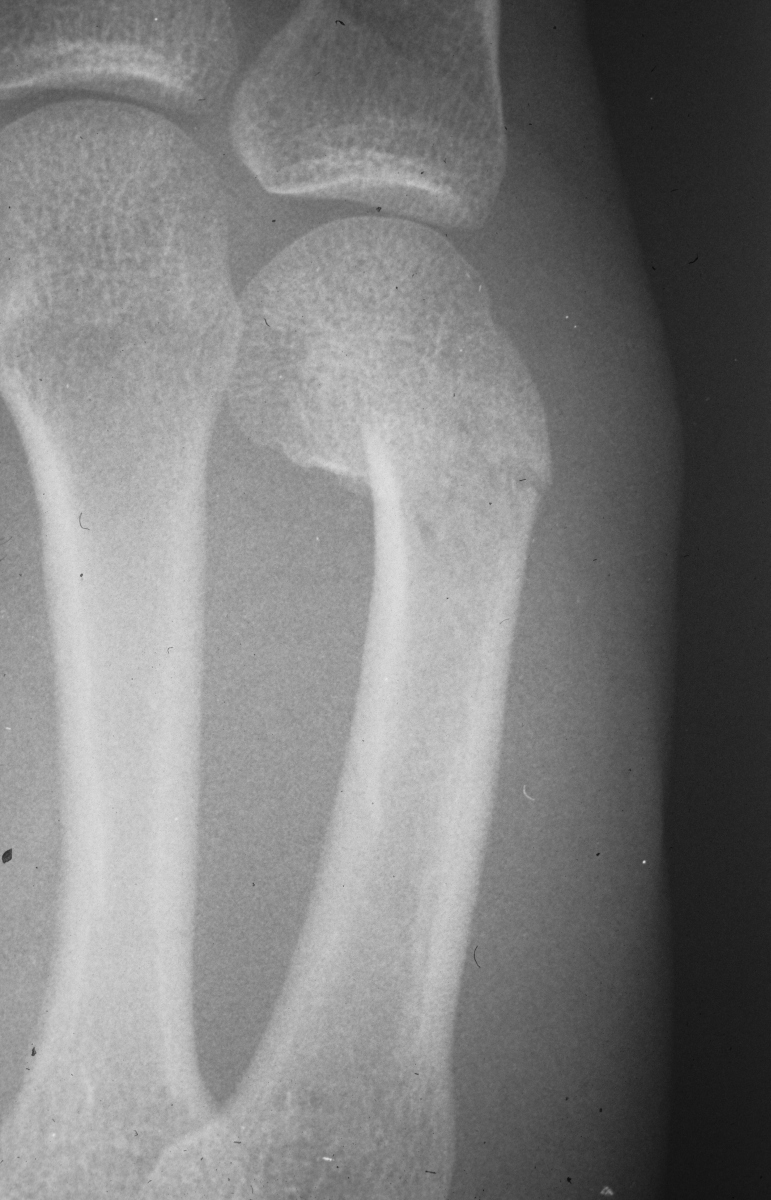

Rotated unstable spiral oblique proximal phalanx

fracture. |

| Reduction and fixation. |

| Appearance at four

weeks. |

| Late result. |